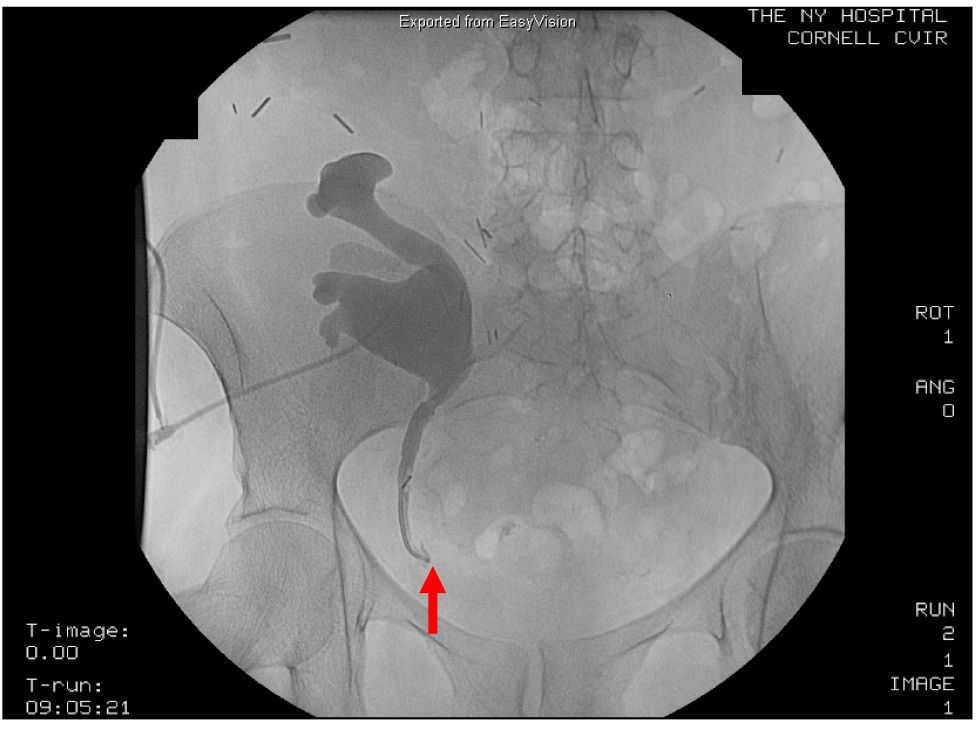

(PDF) Post renal transplant ureteric leak for IR management Post Kidney Transplant Urine Leak Urine leak after kidney transplantation presents with swelling, pain, increased drain output and worsening graft function. These patients should be kept under close monitoring,. Biochemical analysis of the drained. Urine leak is the most common early urologic complication following renal. This article discusses clinical presentation, investigations, and principles of. An analysis of the literature shows that the main focus when. Post Kidney Transplant Urine Leak.